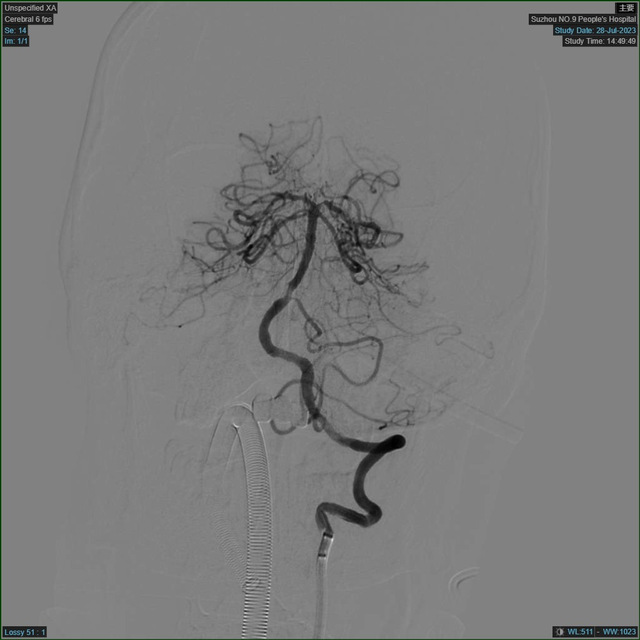

DSA手术室

患者的血管情况远比预计的复杂,维持生命意识的最主要的血管——基底动脉主干发生了闭塞,这样的病变可引起肢体瘫痪、昏迷、甚至死亡。这种手术病变复杂,手术时间长,再通率低,对医生的体力和技术经验都是极大的挑战。医护团队密切协作配合,手术有条不紊地进行,迅速实施脑动脉取栓术。经过2小时的抢救,患者堵塞的血管终于被成功打通,左侧肢体活动明显增多,而此时没有人注意到,手术医师20多斤的铅衣压在身上长达几小时,已经全身湿透。